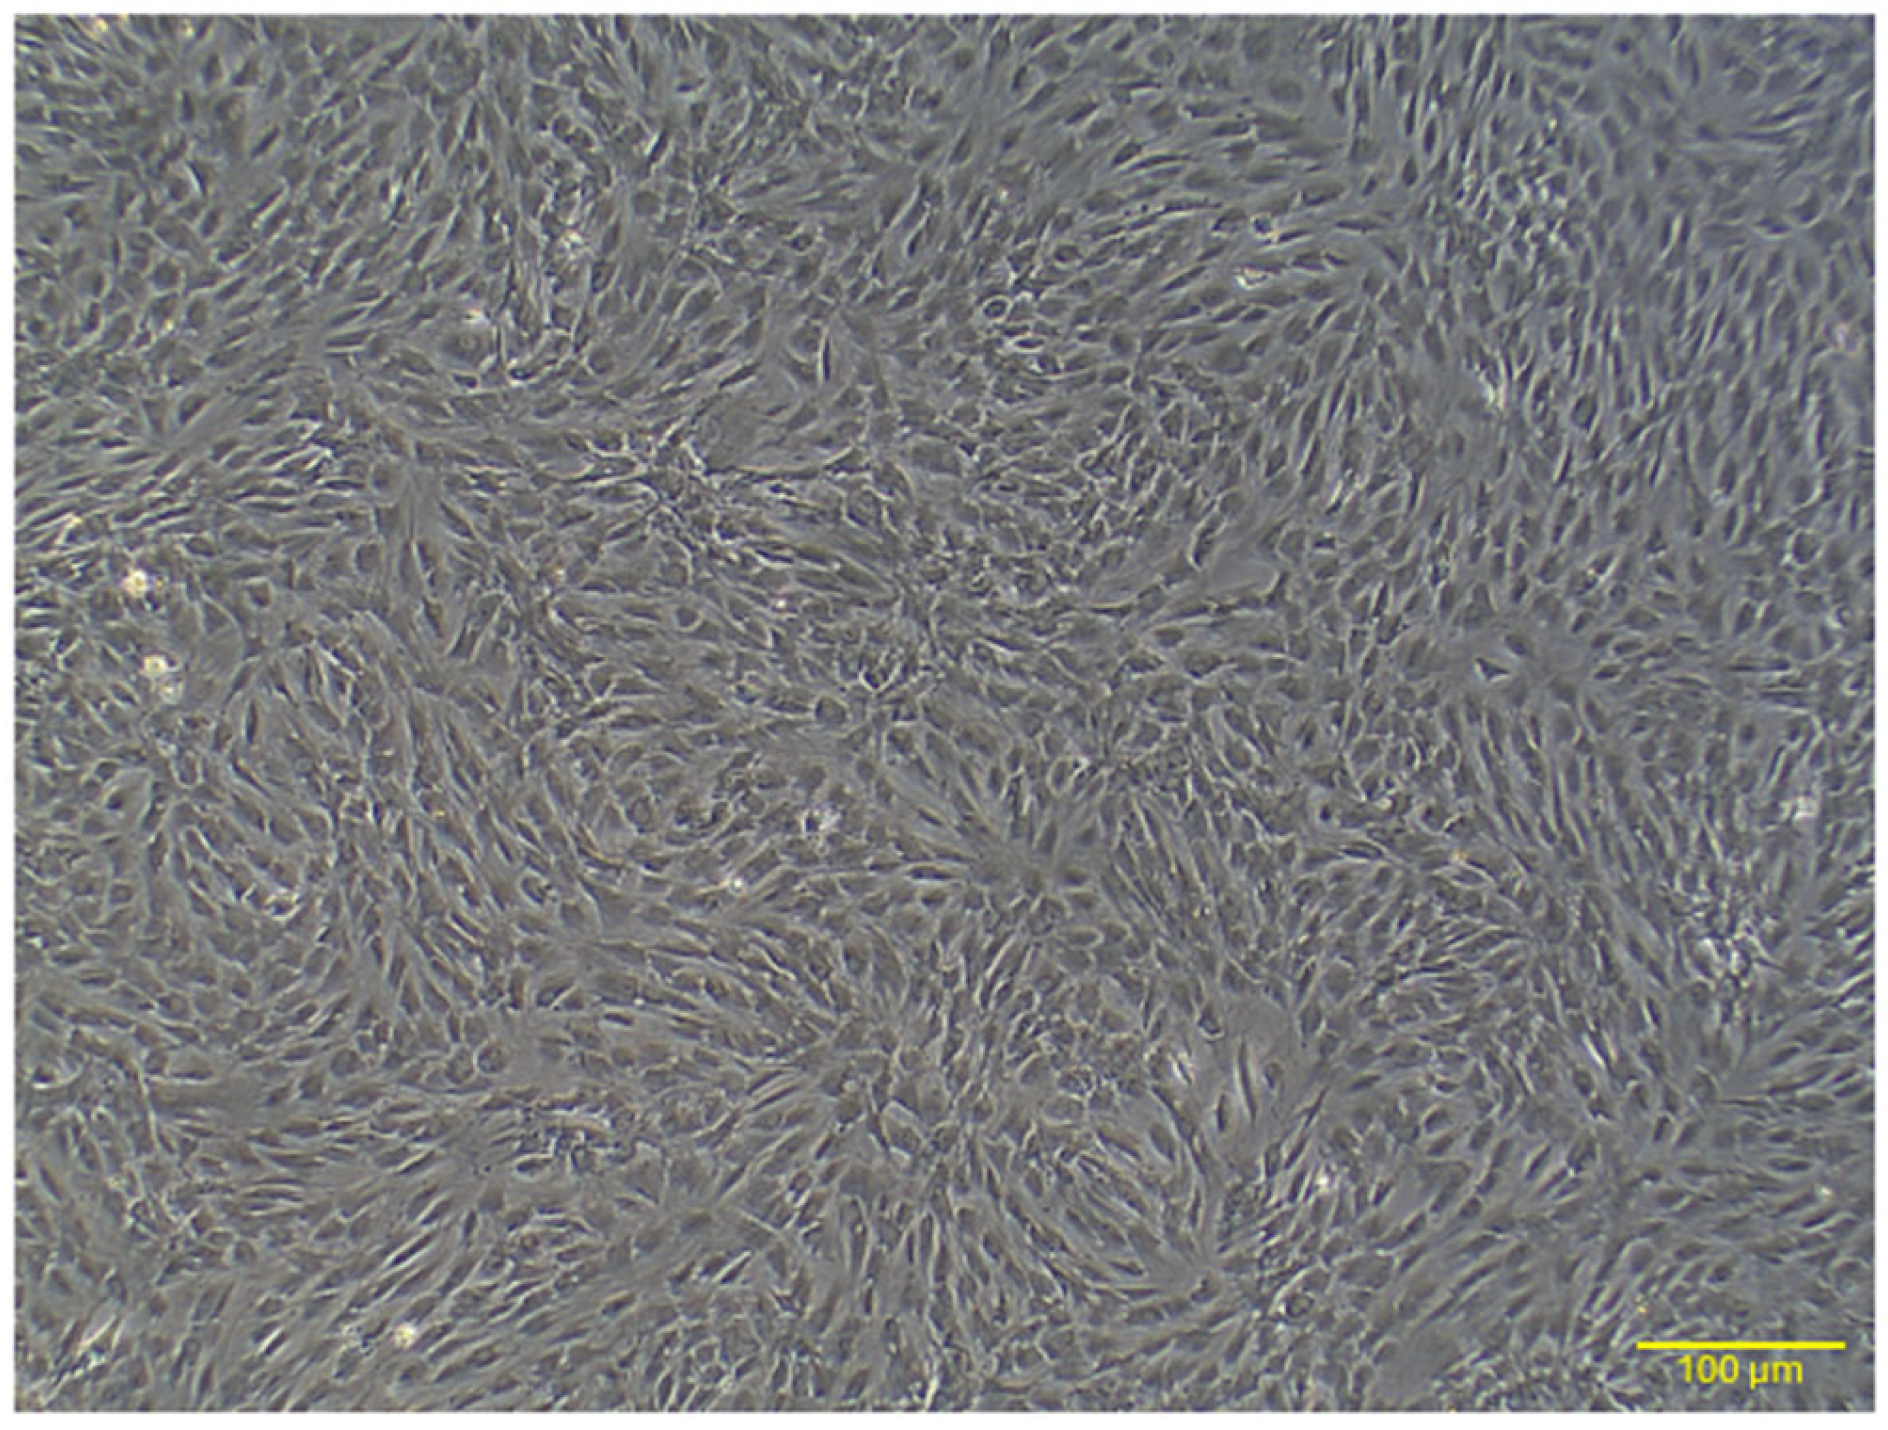

2.1. Characterization of Rat AD-MSCs

2.1.1. Morphology

4.2. Preparation and Culturing of AD-MSCs